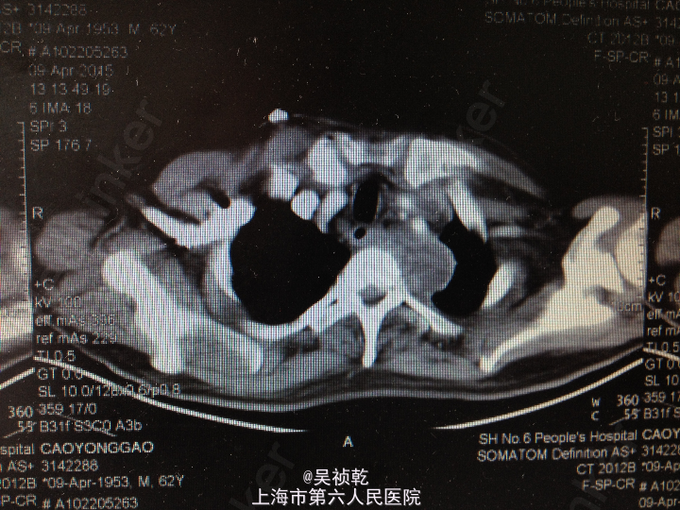

查体:神志清醒,呼吸稍促,推入病房,发育正常,营养良好,自主体位。皮肤粘膜:无黄染,无瘀点瘀斑,无贫血貌,无肝掌,无蜘蛛痣。淋巴结:全身浅表淋巴结可触及肿大。双侧颌下淋巴结肿大,左侧颈部肿大,皮肤红肿,皮温偏高,局部有波动感。头颈部:无头颅畸形,无巩膜黄染,无结膜苍白 ,口唇无紫绀,无扁桃体肿大。颈软,气管居中,甲状腺无肿大,无颈静脉怒张。胸部:胸廓无畸形,心率105次/分, 节律齐,无杂音,两肺呼吸音清,未及啰音。腹部:腹部平坦,腹壁柔软,全腹无压痛、无反跳痛,肝脏肋下未触及,脾肋下未触及,肝区无叩击痛,肾区无叩击痛。无移动性浊音,肠鸣音正常。肛门、直肠及外生殖器: 正常。脊柱与四肢:脊柱无畸形,四肢无畸形,四肢活动自如。神经系统:生理反射存在,病理反射未引出。 辅检:2015-4-8 血气检验报告:二氧化碳分压 34.7 mmHg ↓,氧分压 60.9 mmHg ↓,氧饱和度 91.8 % ↓。门诊化验检验报告:凝血酶原时间 13.1 秒 ,国际标准化比率 1.19 ↑,部分凝血活酶时间 30.4 秒 ,D二聚体 1.13 mg/L FEU ↑,纤维蛋白(原)降解产物 6.4 mg/L ↑。 生化检验报告:肌钙蛋白-I 0.013 ,CKMB 1.4 ug/L ,肌红蛋白 28.6 ug/L 。 生化检验报告:血清钾(干式) 4.5 mmol/L ,血清钠(干式) 137 mmol/L ↓,血清氯(干式) 94 mmol/L ↓,总蛋白(干式) 66 g/L ,白蛋白(干式) 32 g/L ↓,谷丙转氨酶(干式) 26 U/L ,谷草转氨酶(干式) 16 U/L ,γ-谷氨酰酶(干式) 19 U/L ,碱性磷酸酶(干式) 103 U/L ,总胆红素(干式) 16 μmol/L ,尿素(干式) 7.5 mmol/L ↑,肌酐(干式) 67 μmol/L ,尿酸(干式) 154 μmol/L ↓,淀粉酶(干式) <30 U/L ↓,血糖(干式) 22.0 mmol/L ↑,B型钠尿肽前体(proBNP) 199.80 ng/L ↑。 2015-4-9 血常规检验报告:白细胞 13.2 X10^9/L ↑,红细胞 3.76 X10^12/L ↓,血红蛋白 125 g/L ↓,细胞比积 35.8 % ↓,血小板 261 X10^9/L ,淋巴细胞百分比 4.7 % ↓,中性细胞百分比 84.4 % ↑。糖尿病医学中心检验报告:糖化血红蛋白 12.40 % ↑。 颈部超声示:双侧颌下淋巴结肿大,左侧颈后软组织结构紊乱,内混合回声及肿大淋巴结,考虑炎性改变可能,建议治疗后复查。 颈部CT:1.咽后间隙、左侧咽旁间隙及颈动脉鞘软组织明显肿胀、渗出,颈部多发肿大淋巴结,考虑炎症可能大,请结合临床并门诊增强CT评估。2.左侧甲状腺小结节可能,请结合临床,必要时随访。 2015-4-9 颈部增强CT示:颈部及胸腔纵隔脓肿形成。 2015-4-8引流分泌物培养结果: 肺炎克雷伯菌。

患者入院时诊断为:1.左颈部脓肿,颈部软组织感染,纵膈脓肿形成。2.糖尿病。 入院后予对症处理:1.加强抗感染,予万古霉素+磷霉素联合。2.床边行脓肿切开引流,引流液送培养。2、予吸氧、禁食、营养支持等对症治疗。3.病情危重,告知家属相关风险,予告病危。4.进一步完善颈部及胸部增强CT,病请五官科会诊。 2015.04.09CT提示颈部,咽后壁及胸腔纵隔脓肿形成,故请五官科及胸外科会诊,会诊意见为:手术切开引流。故于4.9全麻下行颈部脓肿清创引流术。 手术过程:患者取仰卧位,肩部垫高,全麻达成后,常规消毒铺巾。在胸骨切迹上约两横指处顺皮纹方向作弧形领式切口,长约8cm。依次切开皮肤、皮下组织和颈阔肌。游离颈阔肌深面间隙,在其深面用电刀分离皮瓣,上至甲状软骨切迹,下至胸骨切迹,两侧越过胸锁乳突肌前缘。分离右侧胸锁乳突肌,分离至咽后间隙,咽后间隙内见大量脓液,予双氧水,稀碘伏水,及生理盐水彻底冲洗脓腔。术中请胸外科会诊认为目前上纵隔脓肿暂无需处理。左右各置一根颈部引流管;仔细止血;清点器械无误后,缝合皮下及皮肤层。术中出血少未输血,术程顺利,病人安返。 术后诊断:1.左颈部脓肿,颈部软组织感染,纵膈脓肿形成。2.糖尿病。3.全身感染症状。4.吞咽困难。 术后结合药敏结果,继续予万古霉素+磷霉素联合抗炎,引流管予生理盐水持续冲洗引流,目前引流液不多,术后一周复查CT见脓肿明显缩小,纵膈脓肿有所缩小,目前治疗方案:1.停用原抗菌方案,换用莫比沙星 0.4 qd 静滴,每次滴注90min;2.每3天复查血象,及时复查颈部CT,治疗5天后再评估,一般情况好可停药随访;3.糖尿病患者,注意血糖变化,监测心功能及肝肾功能。